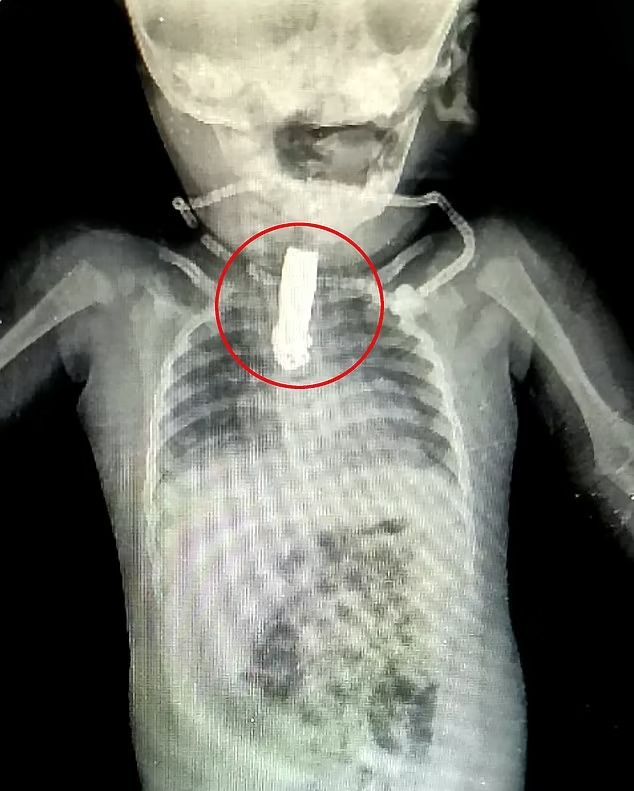

經過X光片照檢查,發現指甲鉗卡在男嬰喉嚨約15cm深處。

在經過X光片照檢查,發現指甲鉗卡在男嬰喉嚨約15cm深處,以醫生波爾(Shashikant Anil Pol)為首組成的醫療團隊,在確定位置後馬上為男嬰進行手術。當時距離男嬰誤吞異物已有2個小時,手術難處在於在男嬰帶來最小的傷害的情況下,取出指甲鉗。